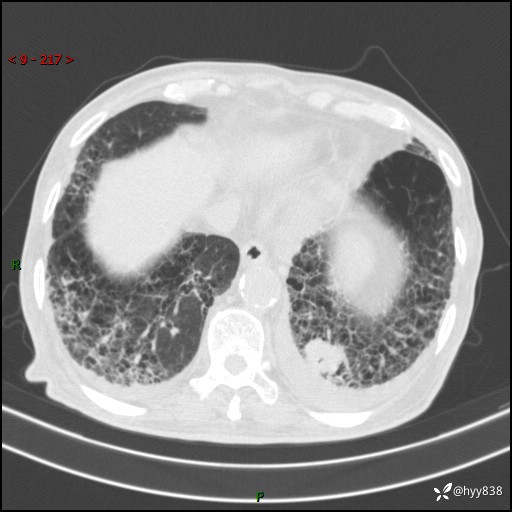

老年男性,间断咳嗽咳痰20余年,加重伴发热1天。呼吸科疑难病例讨论---结果公布

主诉:间断咳嗽咳痰20余年,加重伴发热1天

简要病史:家属代诉患者于20余年前无明显诱因出现咳嗽咳痰,痰为白色泡沫状,未行特殊治疗,不伴胸痛、胸闷、气喘、咳血等不适,1天前上午患者无明显出现发热,查体温39℃,伴咳嗽,咳痰无力,自行予以物理降温对症治疗,今晨2点左右再次出现发热,体温达40℃,自行服用复方氨酚烷胺对症治疗,凌晨3点左右复测体温38.2℃,现患者为求进一步诊治于今日就诊于我院门诊,行胸部CT提示双肺感染,遂以“肺部感染”收入我科。 患者本次起病来精神、食欲、睡眠欠佳,体力下降,体重无明显变化。

辅助检查:CT

临床诊断:感染

讨论:病变性质?

胸部CT平扫